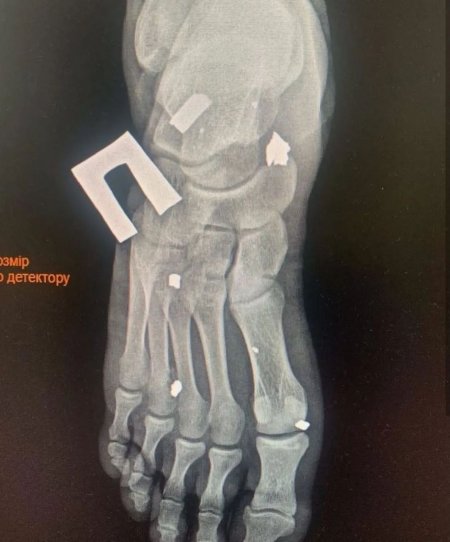

24 листопада під час обстрілу в районі Бахмута Назар отримав тяжкі множинні поранення ніг. Його екстрено прооперували у Дніпрі. Наразі кременчужанин перебуває у госпіталі в Києві.

На його реабілітацію та лікування необхідні фінансові затрати. Лікарі поки ніяких прогнозів не дають, адже уламків у ногах багато.